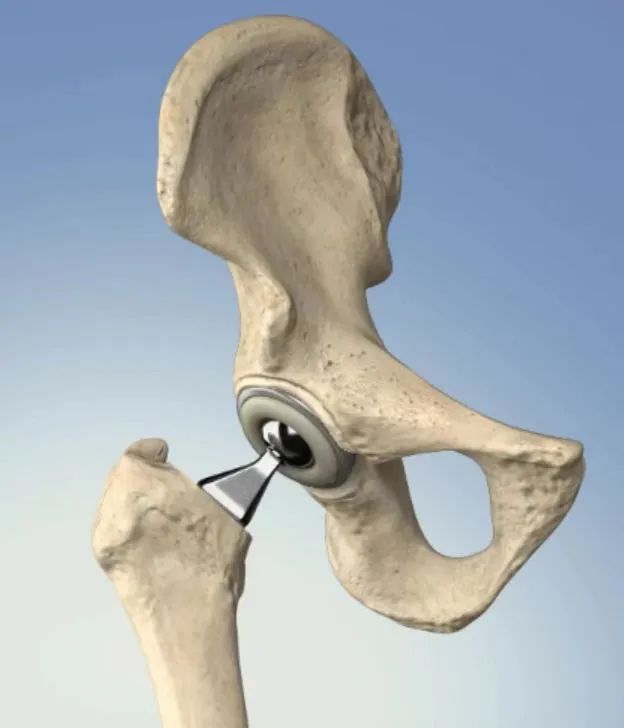

人工髋、膝关节置换是治疗各种原因导致的关节终末期疾病的最有效方法,已经在世界范围内广泛开展。目前,我国人工关节事业进入快速发展阶段,据统计,截至2019年,全国髋、膝关节置换年手术量逾90万台,国产假体构成比例逐年上升。